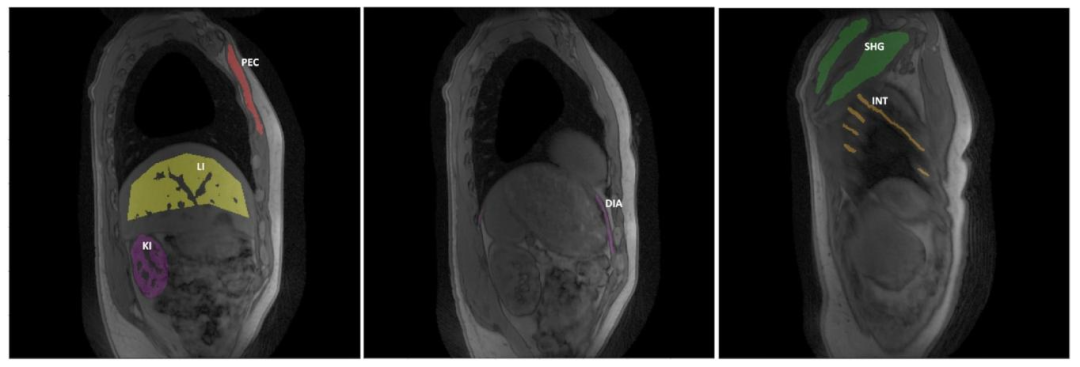

Fig. 6. Representative parametric FF and 𝑇 1𝐻2𝑂 maps obtained at one slice level in a healthy volunteer derived from the uncorrected and motion-corrected (MoCo) MRF T1-FFreconstructions, and from the MRF T1-FF data acquired during the reference respiratory phase only (corresponding to the full-expiration phase). White arrows emphasize regionswhere motion blurring, parameter estimation bias and streaking artifacts are significantly mitigated with the motion correction method.

图6 健康志愿者某一层面的代表性参数FF图和𝑇1𝐻2𝑂图,这些图像分别来源于未校正的MRF T1-FF重建结果、运动校正(MoCo)后的MRF T1-FF重建结果,以及仅在参考呼吸相位(对应完全呼气相位)采集的MRF T1-FF数据。白色箭头标注的区域显示,运动校正方法显著减轻了运动模糊、参数估计偏差和条状伪影问题。